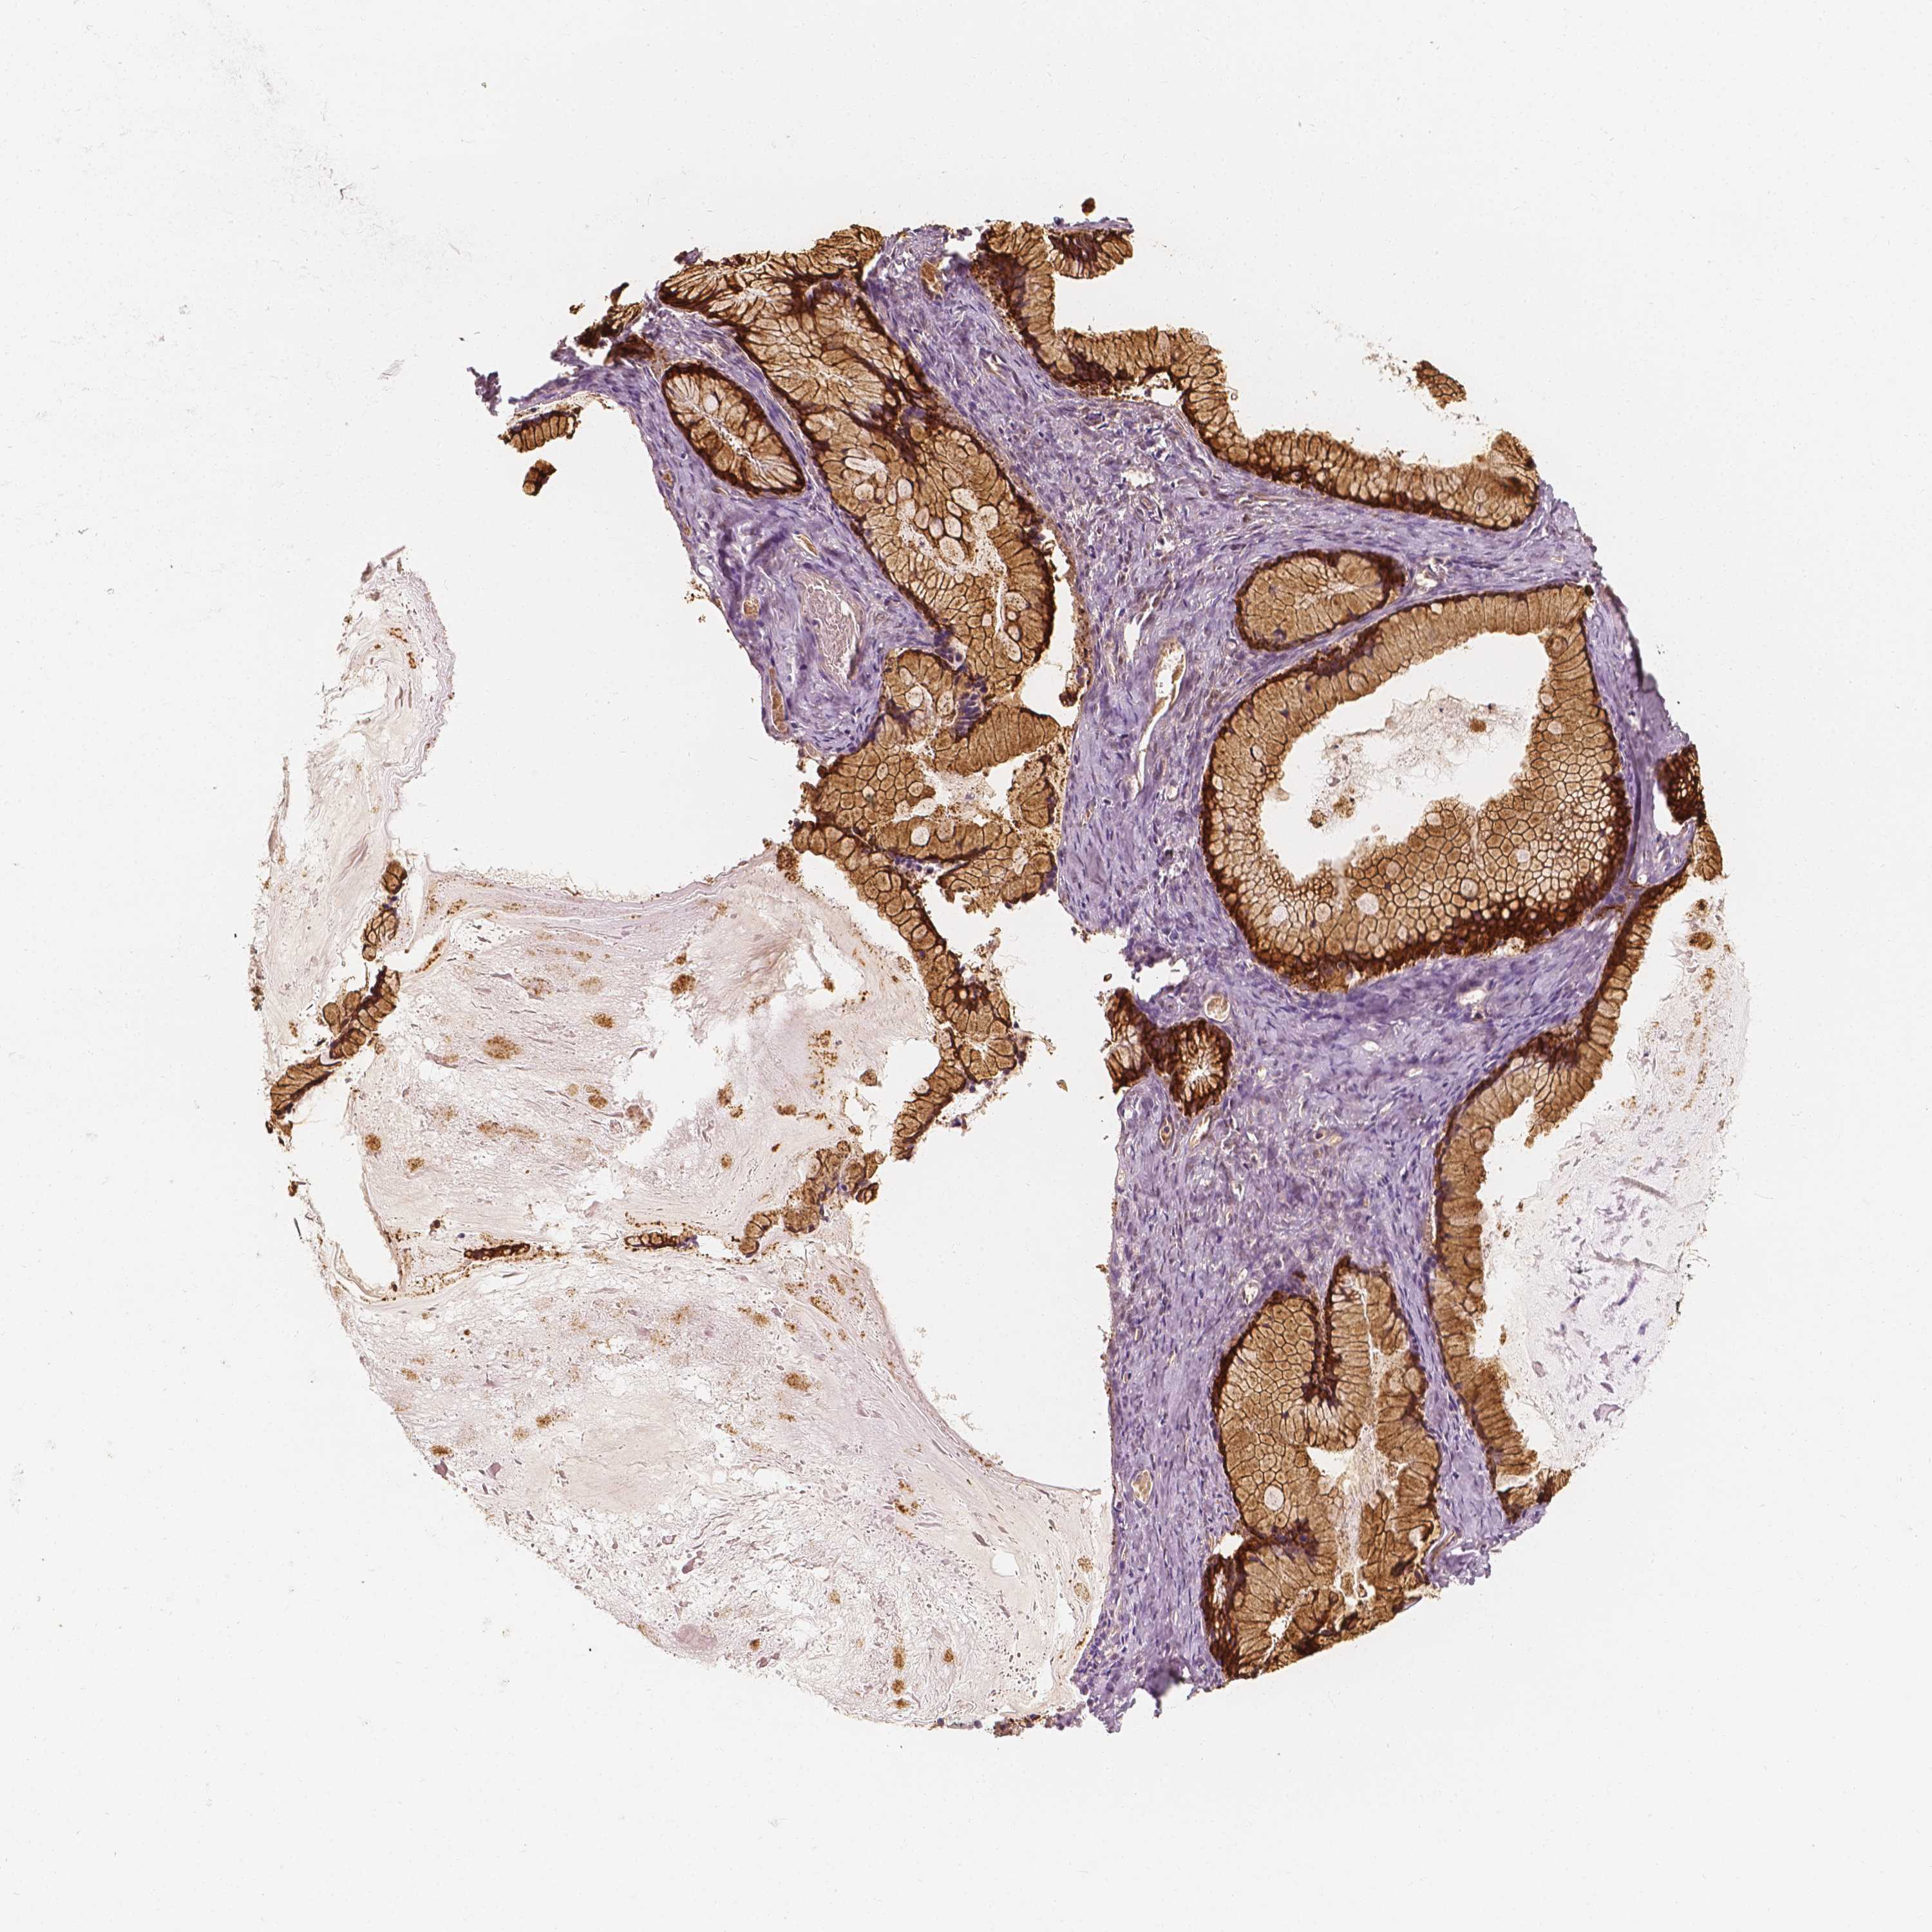

OVARIAN CANCER - Protein expressioni

A mouse-over function shows sample information and annotation data. Click on an image to view it in a full screen mode. Samples can be filtered based on level of antibody staining by selecting one or several of the following categories: high, medium, low and not detected. The assay and annotation is described here.

Note that samples used for immunohistochemistry by the Human Protein Atlas do not correspond to samples in the TCGA dataset.

Antibody stainingi

Antibody staining in the annotated cell types in the current human tissue is reported as not detected, low, medium, or high, based on conventional immunohistochemistry profiling in selected tissues. This score is based on the combination of the staining intensity and fraction of stained cells.

Each image is clickable and will lead to virtual microscopy that enables deeper exploration of all samples and also displays staining intensity scores, fraction scores and subcellular localization as well as patient and tissue information for each sample.

Antibody HPA024361

Antibody HPA064939

Cystadenocarcinoma, serous, NOS

Carcinoma, endometroid

Cystadenocarcinoma, mucinous, NOS

Carcinoma, NOS